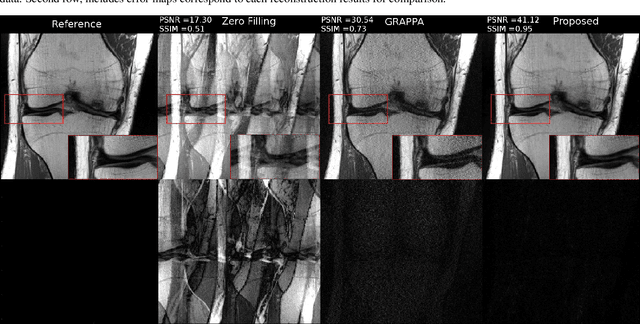

Abstract:Fast data acquisition in Magnetic Resonance Imaging (MRI) is vastly in demand and scan time directly depends on the number of acquired k-space samples. The most common issues in any deep learning-based MRI reconstruction approaches are generalizability and transferability. For different MRI scanner configurations using these approaches, the network must be trained from scratch every time with new training dataset, acquired under new configurations, to be able to provide good reconstruction performance. Here, we propose a new parallel imaging method based on deep neural networks called NLDpMRI to reduce any structured aliasing ambiguities related to the different k-space undersampling patterns for accelerated data acquisition. Two loss functions including non-regularized and regularized are proposed for parallel MRI reconstruction using deep network optimization and we reconstruct MR images by optimizing the proposed loss functions over the network parameters. Unlike any deep learning-based MRI reconstruction approaches, our method doesn't include any training step that the network learns from a large number of training samples and it only needs the single undersampled multi-coil k-space data for reconstruction. Also, the proposed method can handle k-space data with different undersampling patterns, and different number of coils. Unlike most deep learning-based MRI reconstruction methods, our method operates on real-world acquisitions with the complex data format, not on simulated data, real-valued data, or data with added simulated-phase. Experimental results show that the proposed method outperforms the current state-of-the-art GRAPPA reconstruction method.